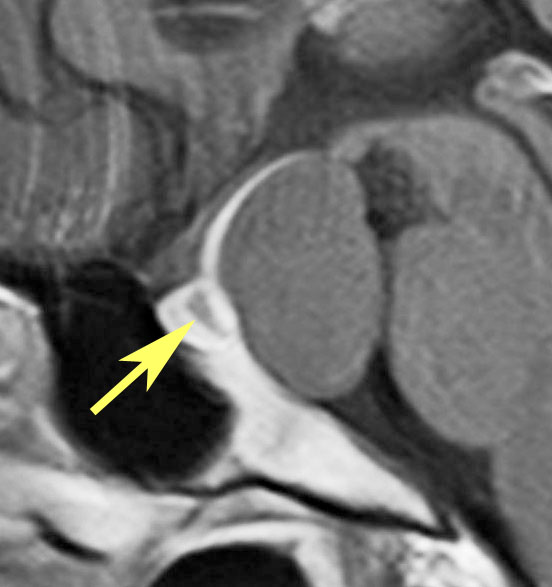

下垂体柄の周囲にのう胞性腫瘍があります。T1強調画像では等信号,T2強調画像ではまだらな信号になっています。23年という長い経過から液状内容物が固形化したものと推定されます。T2で低信号となる部分があるのですが,黄色肉芽腫とは異なる像です。

下垂体柄は長く伸びています。のう胞による長期の圧迫のため斜台上部がerosionになって凹んでいます。トルコ鞍内の中間葉の位置に典型的な小さなラトケのう胞(黄色矢印)がみられますが,これは長年変化していませんでした。

左前頭側頭開頭 pterional approachで,のう胞壁を含めて完全摘出 complete removalしました。のう胞は下垂体柄の左側に付着してそこから発生したものでした。内容物は固体で寒天状のコロイドでした,一部軟らかくて一部は線維化していました。のう胞壁は半透明で薄い部分も線維性の膜状の部分もありました。病理検査では上皮細胞が証明されて内胚葉のう胞 endodermal cystの診断です。